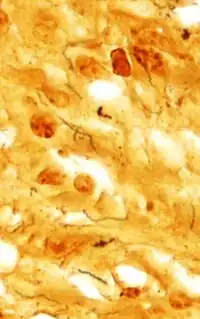

Treponema pallidum was first microscopically identified in syphilitic chancres by Fritz Schaudinn and Erich Hoffmann at the Charité in Berlin in 1905.[28] This bacterium can be detected with special stains, such as the Dieterle stain. T. pallidum is also detected by serology, including nontreponemal VDRL, rapid plasma reagin, treponemal antibody tests (FTA-ABS), T. pallidum immobilization reaction, and syphilis TPHA test.[29]